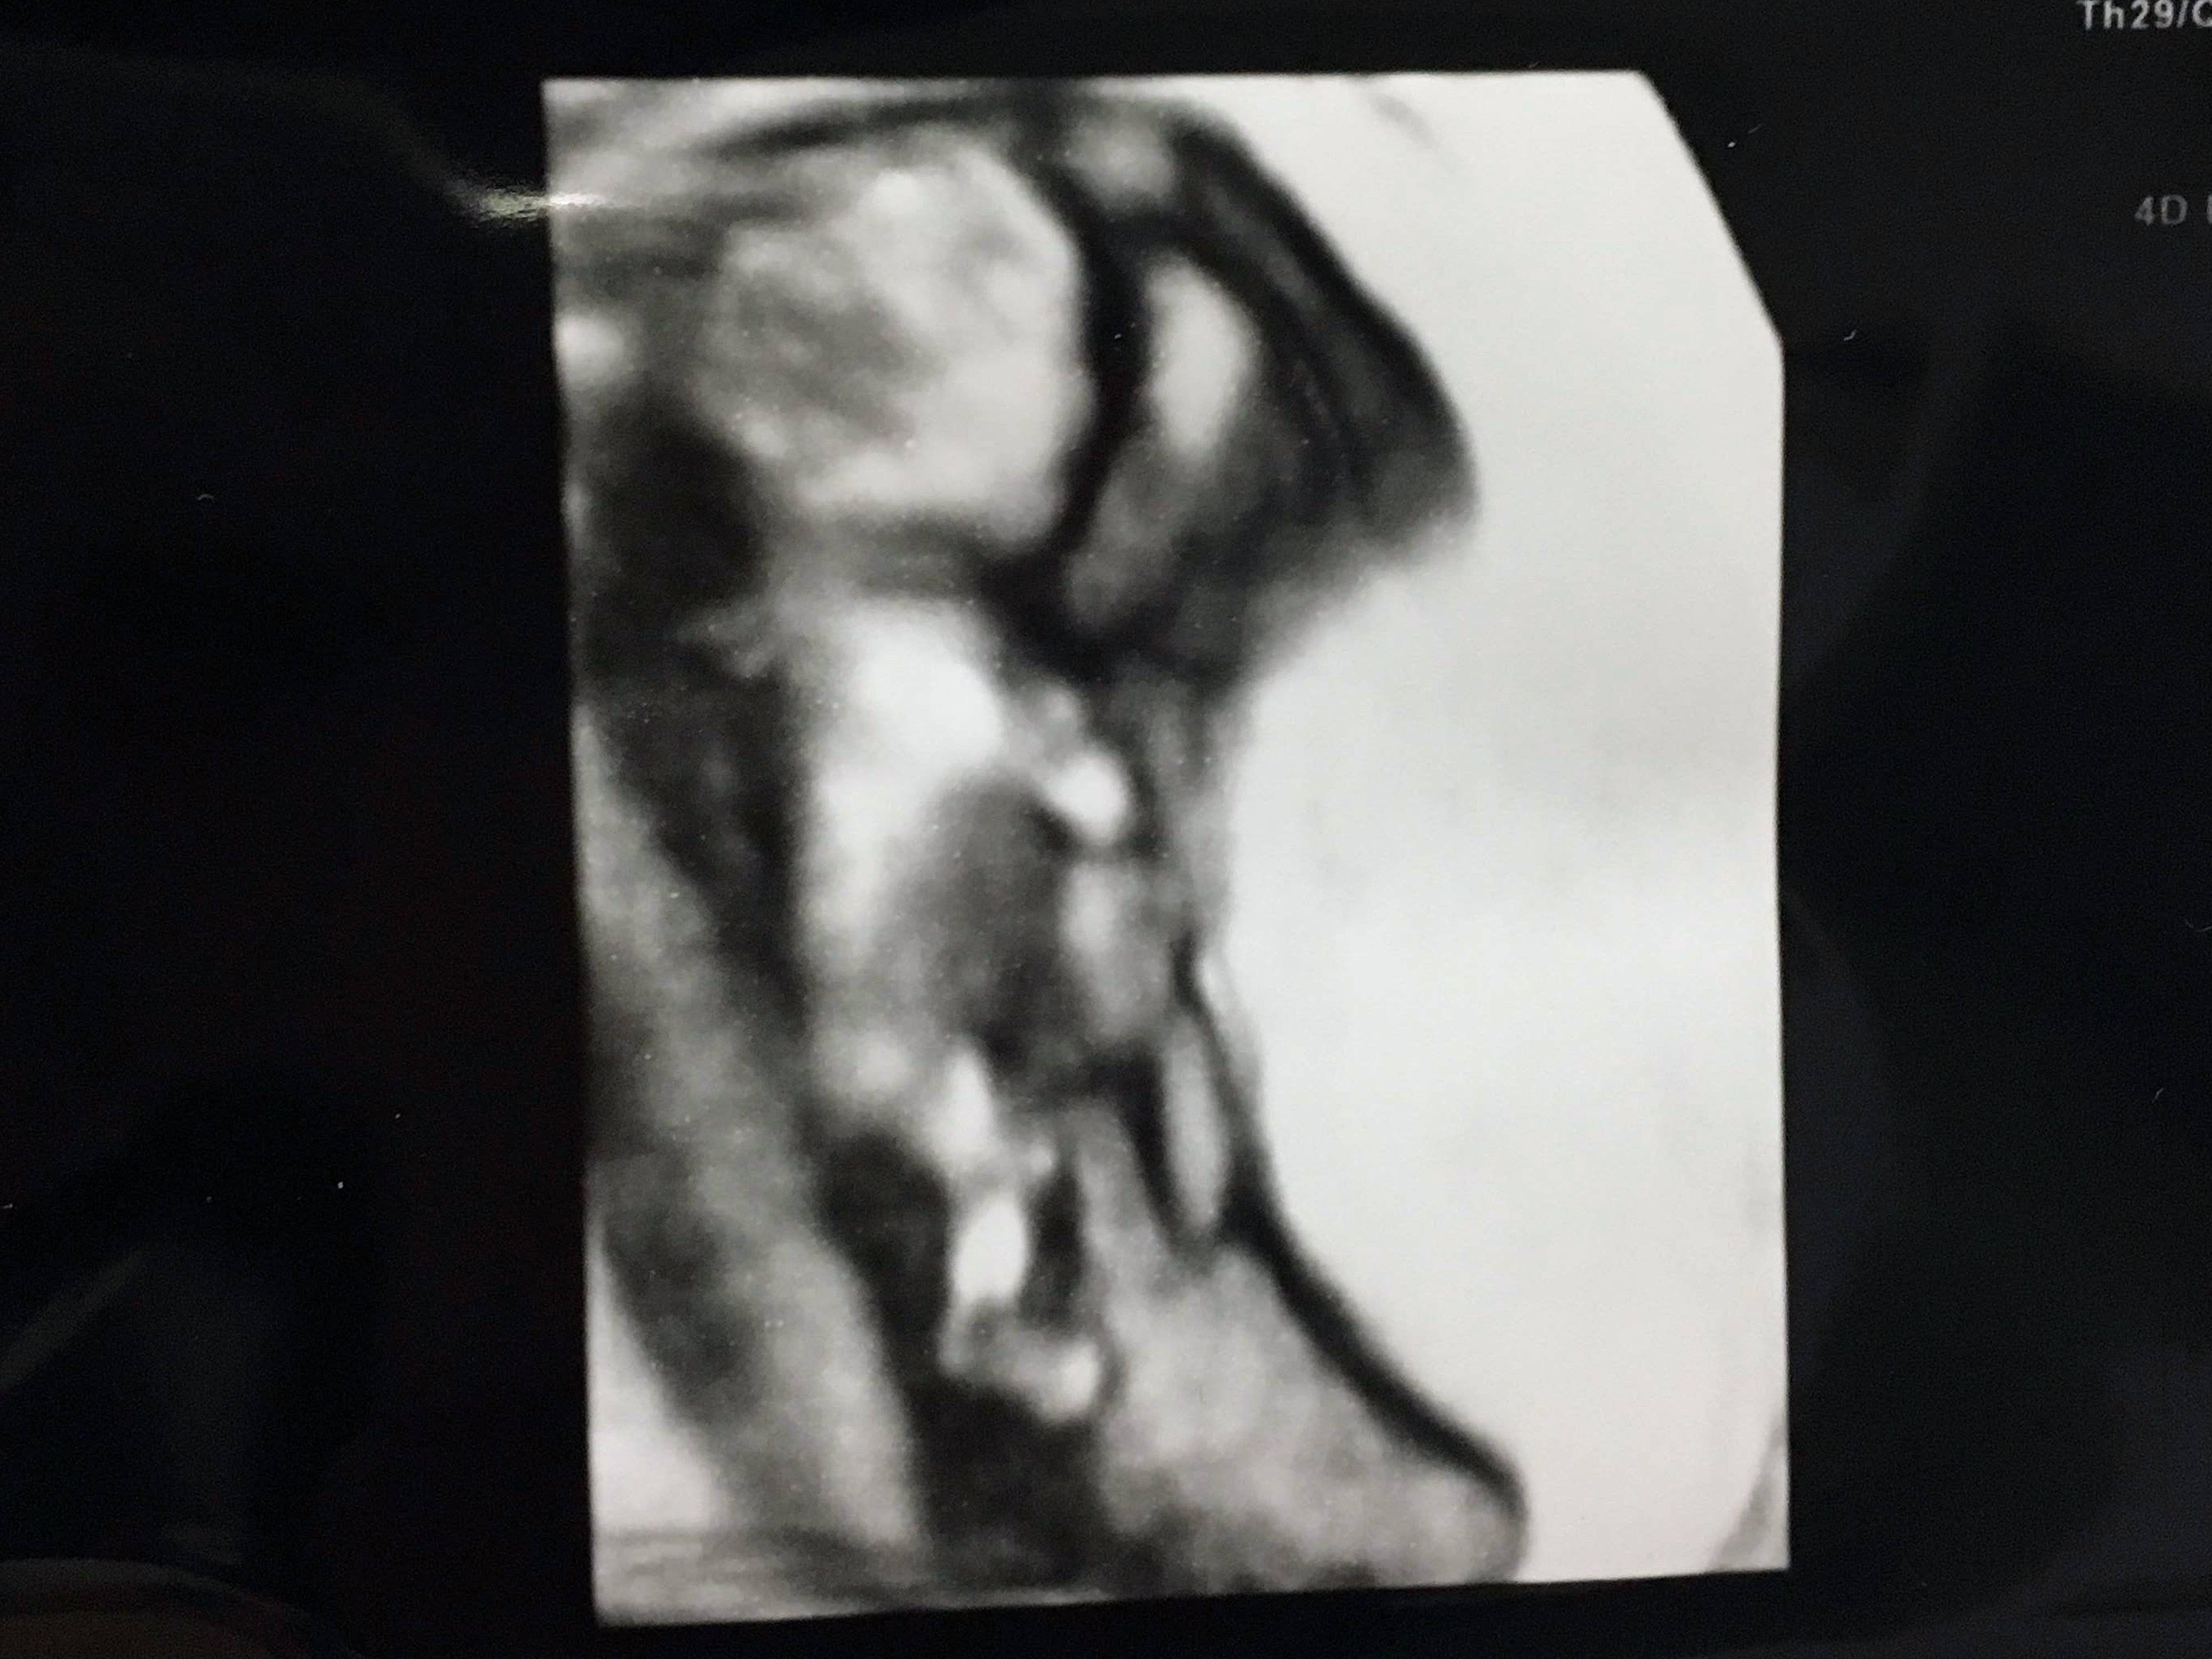

妊娠12週目 4Dエコーで、手足もはっきり見えた!

初めての4Dエコー写真です。左上にあるのが頭で、縦になっています。

小さな足や腕もはっきりと見えました。まだ安定期に入っていなかったため、周囲には妊娠していることを話していませんでした。しかし、つわりは悪化するばかり。

「急に瘦せちゃってどうしたの?」と心配されました。まだ胎動もなかったので、エコーで子どもの様子を見られるのがとても楽しみでした。